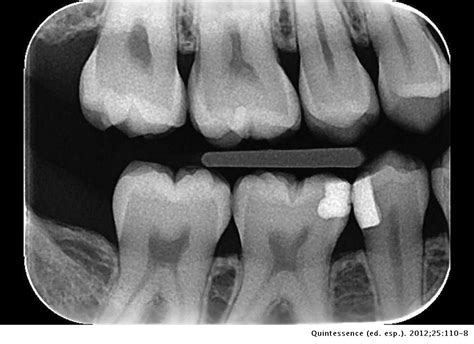

Tratamiento de Restauración Dental y Espacio Interproximal

El espacio interproximal, interdental o interdentario es el espacio que existe entre un diente y sus contiguos. En estos espacios, causados por múltiples factores, se pueden acumular restos de comida facilitando la aparición y acumulación de placa bacteriana.